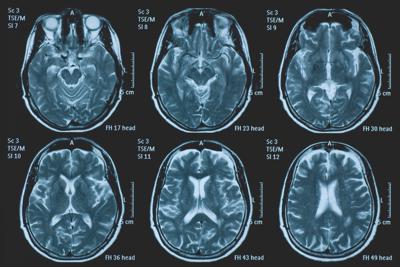

Roma, 23 apr. (Adnkronos Salute) – La Commissione europea (Ce) ha autorizzato la commercializzazione condizionata di tovorafenib come monoterapia per il trattamento dei pazienti di età pari o superiore a 6 mesi con glioma pediatrico di basso grado che presentano una fusione o un riarrangiamento del gene Braf o una mutazione Braf-V600, in progressione di malattia dopo una o più terapie sistemiche precedenti. Lo annuncia Ipsen, in una nota, precisando che si tratta della “prima terapia mirata” per questa patologia e che la decisione della Ce si riferisce ai 27 Stati membri della Ue, oltre a Islanda, Liechtenstein e Norvegia. Ogni anno in Ue vengono diagnosticati più di 800 nuovi casi di glioma pediatrico di basso grado (pLgg) con alterazione di Braf. Questo tumore cerebrale, nonostante sia classificato di basso grado (a lenta progressione), comporta un carico significativo e permanente che accompagna la persona per tutta la vita, causando spesso importanti compromissioni fisiche e neurologiche, tra cui perdita della vista, difficoltà di linguaggio e disfunzioni motorie, che possono incidere in modo significativo sull’istruzione, l’autonomia e la qualità di vita a lungo termine del bambino. Finora, molti bambini con pLgg hanno dovuto sottoporsi a interventi chirurgici invasivi, a più cicli di chemioterapia e a radioterapia, con conseguenti complicazioni della salute.